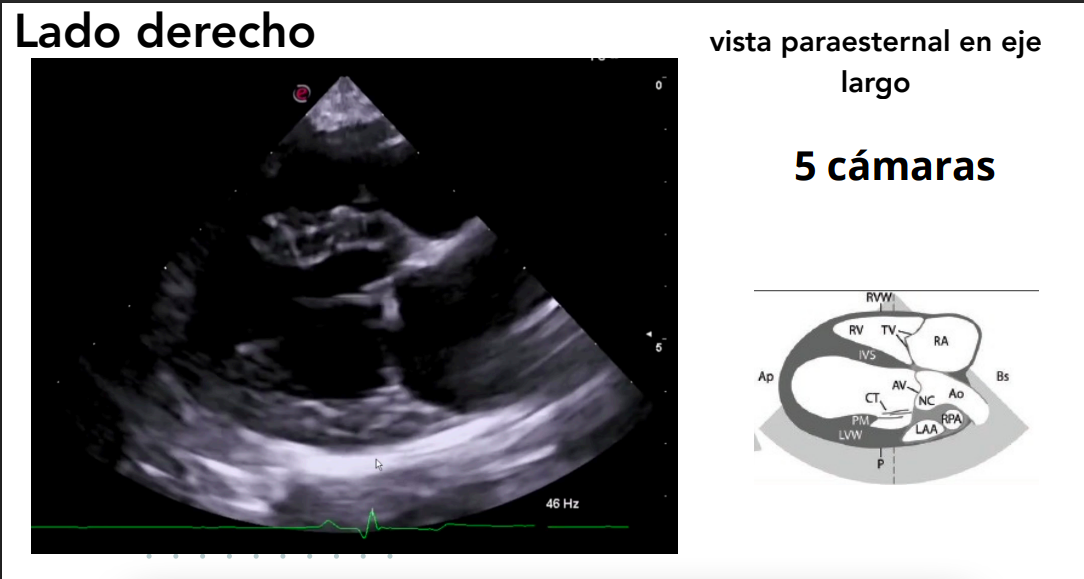

1. Lado derecho

Posición: decúbito lateral derecho.

- El transductor se coloca en el 4º-5º espacio intercostal, a 1–5 cm del borde esternal. Por eso se llama paraesternal.

- Se obtienen vistas paraesternales (ejes largos y cortos).

Ejes:

- Largo (longitudinal): del eje base–ápex.

- Corto (transversal): perpendicular al eje largo.

Vista paraesternal en eje largo

- 4 cámaras y 5 cámaras (incluye tracto de salida del VI).

- Evaluación de:

- Válvulas mitral, tricúspide y aórtica.

- Regurgitaciones valvulares.

- Defectos en septos interatrial e interventricular.

Doppler color: muestra regurgitaciones.

Doppler espectral: analiza velocidades de flujo.